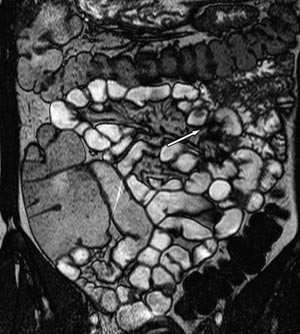

Bruk av sonde gir god utvidelse av både jejunum og ileum (fig 2). Duodenum blir vanligvis ikke fylt med væske fordi sondeballongen hindrer refluks. Av og til vil heller ikke proksimale jejunum bli fremstilt fordi sonden vandrer i distal retning. Den største ulempen med metoden er likevel nedleggelsen av sonden. Pasientene opplever dette som ubehagelig, og prosedyren innebærer fortsatt noe strålebelastning. Det er derfor stor interesse for MR-undersøkelse av tynntarm med oral kontrast.

Vanlige MR-funn ved Crohns sykdom er fortykket tarmvegg (fig 5). Mer overflatiske forandringer i slimhinnen blir ikke optimalt fremstilt, men dypere ulcuser blir fremstilt, og dette er tegn på aktiv inflammasjon (fig 6). Både fibrose og aktiv inflammasjon i tarmveggen lader opp etter intravenøs kontrast. Det typiske for aktiv inflammasjon er en kraftig og lagdelt kontrastoppladning (fig 7), men den kan også være mer homogen.

Vår erfaring med MR av tynntarm skriver seg i hovedsak fra undersøkelser av pasienter med Crohns sykdom. Det finnes flere studier der man har sammenliknet MR av tynntarm med sonde og røntgen tynntarm med sonde med kliniske funn hos pasienter med denne sykdommen (1) – (6). Disse studiene viser at MR-undersøkelse er like bra som konvensjonell tynntarmsrøntgen for fremstilling av dype ulcuser og stenoser. Sensitiviteten var 100 % og spesifisiteten 75 % for fremstilling av dype ulcuser (3). Stenose ble påvist med en sensitivitet og en spesifisitet på 100 % (2, 3). Forandringer utenfor tarmen, som abscess og fistel, ble påvist i større grad med MR enn med konvensjonell røntgen og med en sensitivitet på henholdsvis 80 % og 70 % (4). I en studie fra 2004 ble MR-funn og røntgenfunn proksimalt for terminale ileum sammenliknet hos pasienter med kjent Crohns sykdom i colon eller terminale ileum (6). Det var samme funn i terminale ileum hos 23 av 25 pasienter med MR og med endoskopi. Ved hjelp av MR ble det påvist flere lesjoner proksimalt for terminale ileum enn det som ble påvist med konvensjonell røntgen. Overflatiske ulcuser er vanskelig å fremstille på MR pga. for lav bildeoppløsning. Disse fremstilles bedre med konvensjonell røntgen av tynntarm med sonde (3).